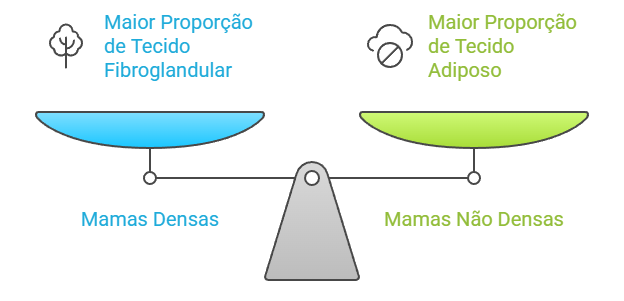

Nossas mamas são compostas por três tipos principais de tecidos:

- Tecido glandular: responsável pela produção de leite durante a lactação

- Tecido fibroso: oferece sustentação e forma à mama

- Tecido adiposo (gordura): preenche o restante da estrutura mamária

Quando falamos em “mamas densas”, significa que existe uma proporção maior de tecido fibroglandular (glandular e fibroso) em comparação ao tecido adiposo. É como se sua mama tivesse mais “estrutura” e menos gordura. Na mamografia, o tecido fibroglandular aparece branco, enquanto a gordura aparece escura (cinza).